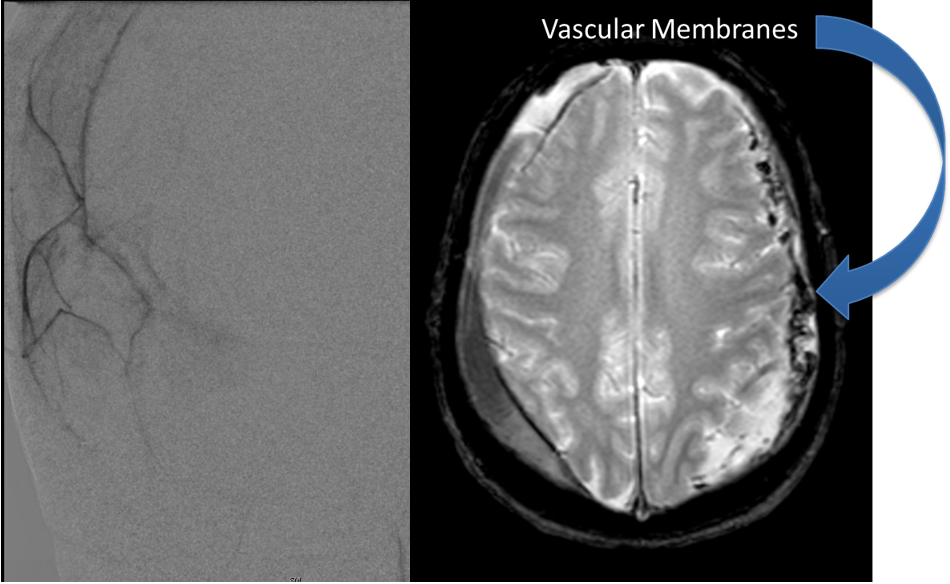

Brain:

Neurosurgeons Collaborate to Treat Giant Symptomatic Meningioma

Author: Ramin Rak M.D., F.A.A.N.S., F.C.N.S., Jonathan L. Brisman M.D., F.A.C.S., Read More!